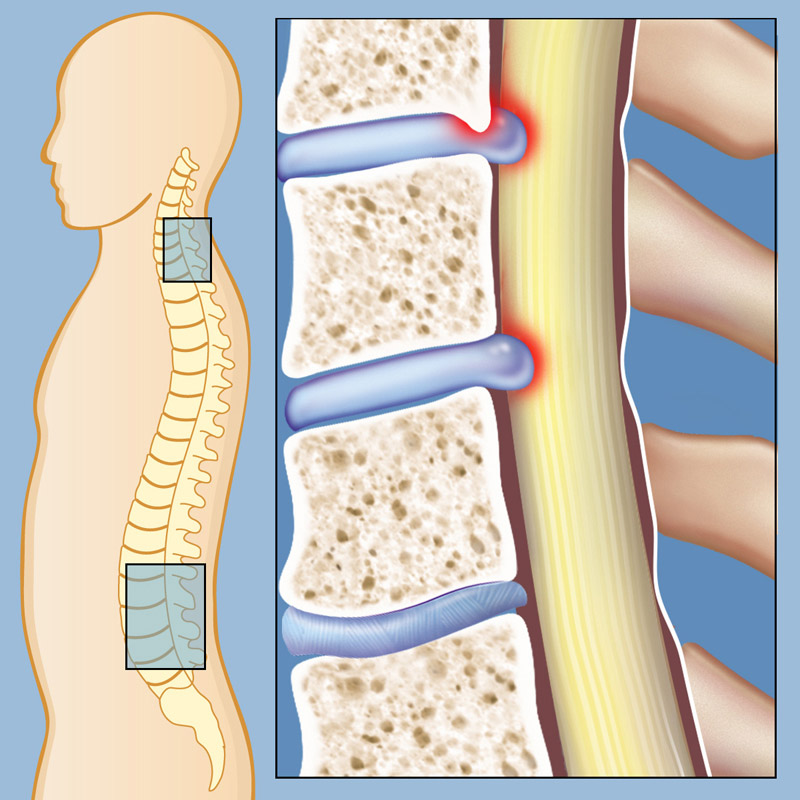

Spinal Stenosis – ONZ Spine

What is a spinal disc bulge or herniation? – DR. JASON ADAMS B.HSC, D.C …

Spinal Stenosis | Weill Cornell Brain and Spine Center